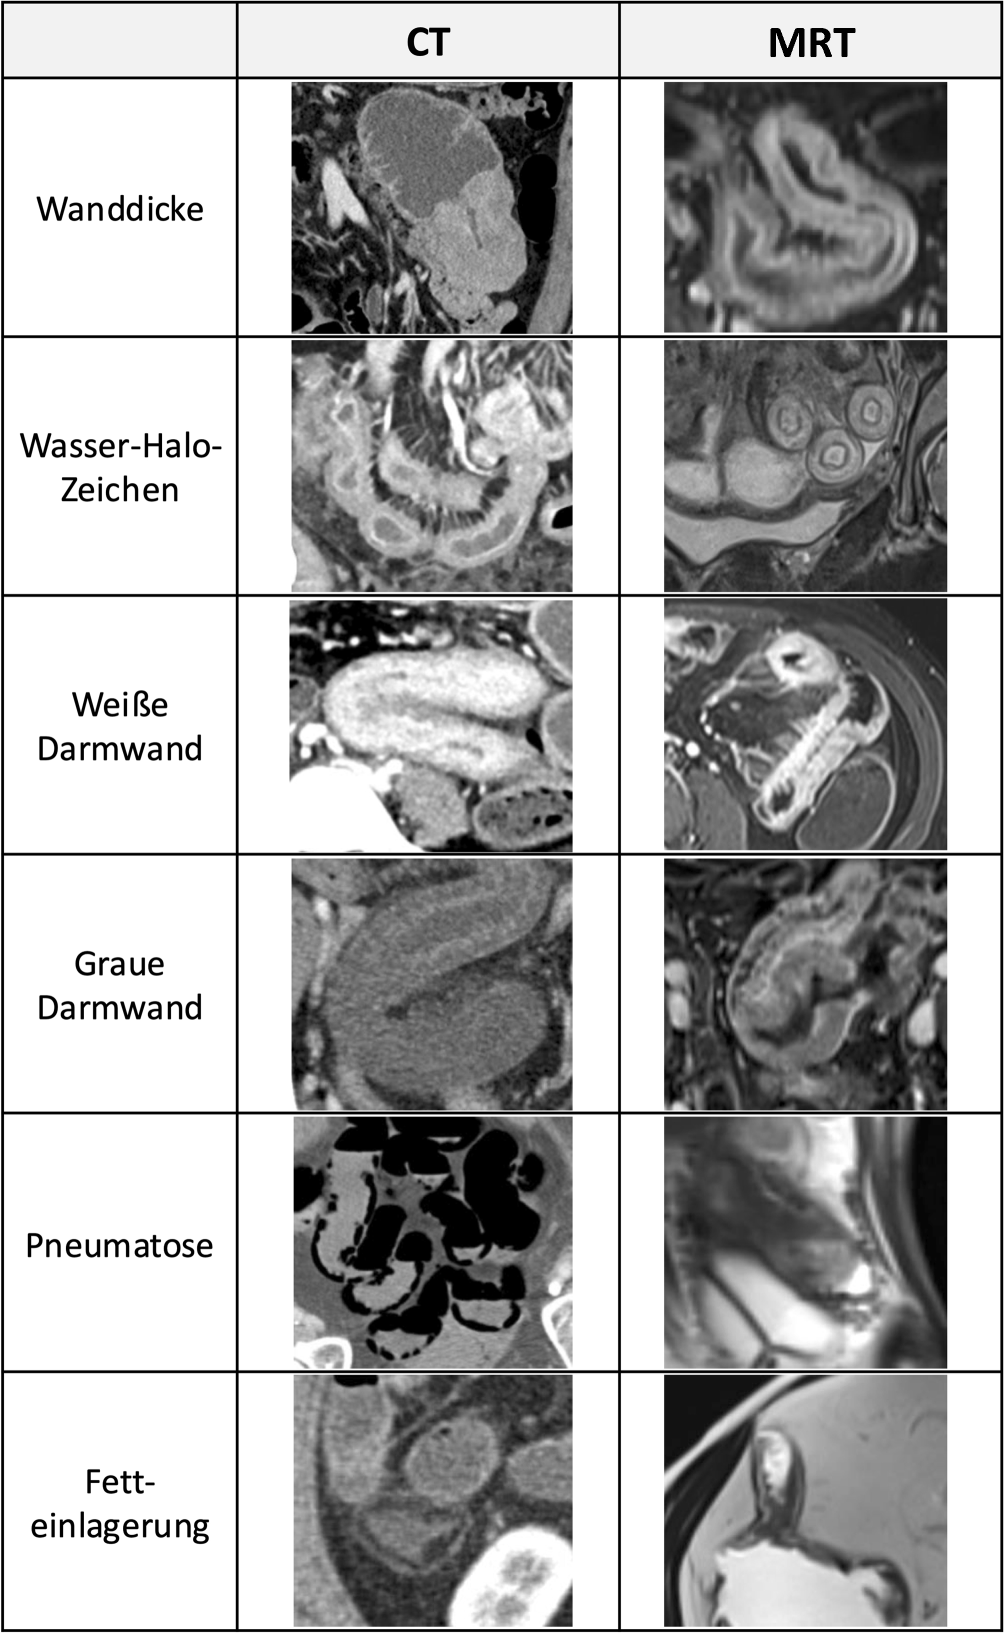

Unterschiedliche Muster der muralen Kontrastmittelaufnahme und ödematöse, fettige oder gashaltige Einlagerungen in einzelne Wandabschnitte können zu charakteristischen Schichtungsphänomenen führen [26]. Diese werden im Querschnittsbild begutachtet und sind differenzialdiagnostisch hilfreich.

Unterschieden werden die weiße und die graue Darmwand, das Wasser-Halo- und das Fett-Halo-Zeichen sowie die schwarze Darmwand.

Eine weiße Darmwand resultiert aus einer homogenen diffusen muralen Kontrastmittelaufnahme infolge einer Vasodilatation, die einen bildmäßig hellen, „weißen“ Aspekt der Darmwand ergibt. Sie findet sich in akuten Phasen chronisch-entzündlicher Darmerkrankungen, im Rahmen eines Schockgeschehens (Schockdarm), bei Reperfusionsödem nach Ischämie oder auch bei intramuralen Hämatomen aufgrund einer muralen Bluteinlagerung.

Das Bild einer grauen Darmwand ergibt sich hingegen aus einer fehlenden oder reduzierten Kontrastmittelaufnahme. Pathophysiologisch liegen diesem Bild häufig eine Minderperfusion bei Ischämie, chronisch-entzündliche bzw. fibrotische Veränderungen (z. B. M. Crohn) oder eine tumoröse Veränderung (Adenokarzinom, Lymphom) zugrunde.

Das Wasser-Halo-Zeichen oder Schießscheibenzeichen in Form von konzentrischen Ringen findet sich typischerweise bei einem Ödem der Darmwand. Die murale Flüssigkeitseinlagerung führt in Schnittbilduntersuchungen zu einer Zwei- oder Dreischichtung der Darmwand, die durch eine verstärkte Kontrastmittelaufnahme der Mukosa und ggf. der Lamina muscularis propria/serosa hervorgehoben wird. Das submuköse Ödem stellt sich in der CT als vergleichsweise hypodensere mittlere Schicht dar. In der MRT ist es in T2-fettunterdrückten Sequenzen stark hyperintens. Im Querschnitt ergibt sich der Aspekt von konzentrischen Ringen, die an eine Schießscheibe erinnern (Target- oder Schießscheibenzeichen).

Dieses unspezifische Muster findet sich typischerweise bei akuten Erkrankungen wie infektiöser Enteritis, akuten Schüben eines M. Crohn, ischämischer oder radiogener Enteritis sowie einer Graft-versus-host-Erkrankung („graft-versus-host disease“, GvHD).

Fetteinlagerungen in der Submukosa können bei langjährigem M. Crohn, nach Chemo- oder Strahlentherapie und im Rahmen einer Zöliakie auftreten. Sie finden sich aber auch bei gesunden Personen und bei adipösen Menschen.

Die schwarze Darmwand (Pneumatosis intestinalis) entsteht durch intramurale Gasansammlungen mit zystischem oder linearem Aspekt. Eine intestinale Pneumatose gilt als potenzielles Alarmsignal für eine kritische Darmischämie, kann jedoch auch bei einer Vielzahl benigner Zustandsbilder mit gestörter Mukosabarriere vorkommen, etwa bei COPD („chronic obstructive pulmonary disease“), Kollagenoasen oder idiopathischen Formen, die bevorzugt das Kolon betreffen [27].

Abb. 7 zeigt die verschiedenen Darmwandmuster und ihr Erscheinungsbild in der CT sowie der MRT.

Abb. 7

Darmwandmuster in der Computertomographie (CT) und in der Magnetresonanztomographie (MRT)